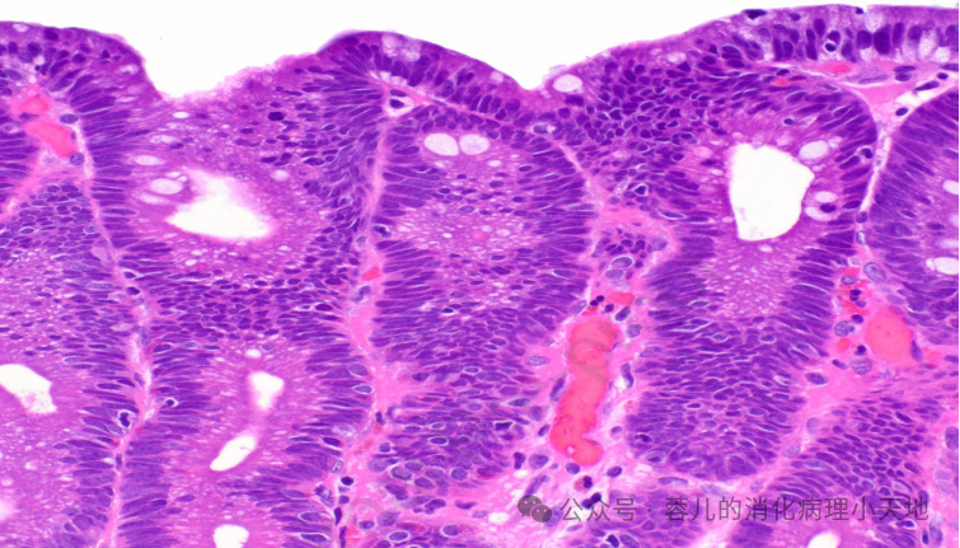

不完全肠上皮化生:由杯状细胞组成,中间夹杂着缺乏吸收细胞的胃小凹型细胞,显示刷状缘

完全肠上皮化生,伴有杯状细胞和结构完整的刷状缘

病变细胞缺乏粘蛋白,并含有铅笔状假复层核,这些核保持与基底膜的关系